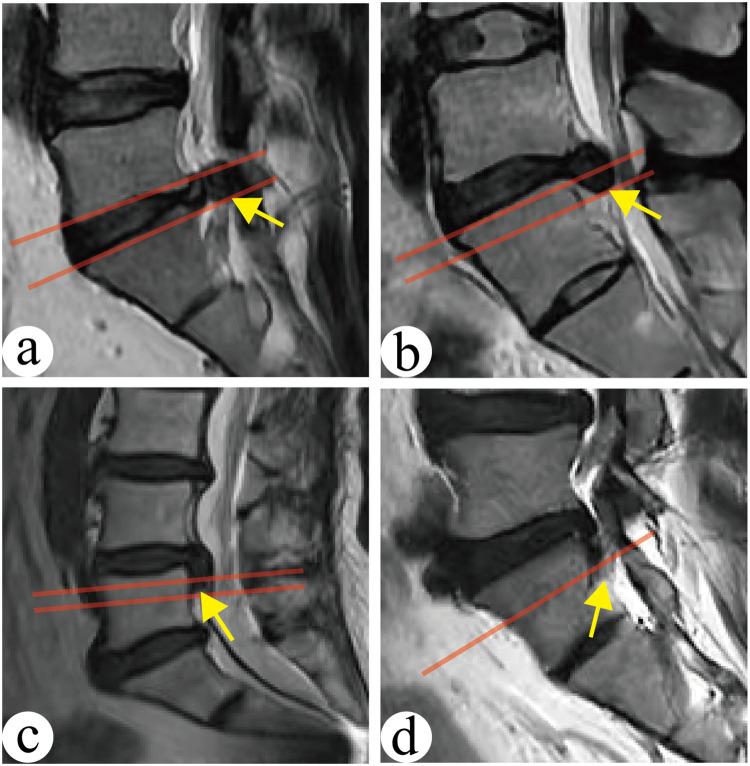

To investigate the surgical method and efficacy of percutaneous endoscopic transforaminal discectomy (PETD) for the treatment of lumbar disc herniation (LDH) with different migration levels by introducing the strategy of foramenoplasty with the "distal nucleus pulposus as the core".

Clinical data of LDH patients who underwent single-segment PETD surgery were retrospectively analyzed. Three groups were categorized according to the degree of nucleus pulposus migration in the sagittal position: no migration group, mild migration group, and high migration group. Different sites of foramenoplasty were used for LDH with different degrees of migration. All patients were followed up for at least 12 months. The clinical and follow-up data of the three groups were compared.

PETD is effective in the treatment of LDH with different degrees of migration, and the foramenoplasty concept of "distal nucleus pulposus as the core" can effectively guide the molding site of foramenoplasty and facilitate the accurate placement of the working trocar.